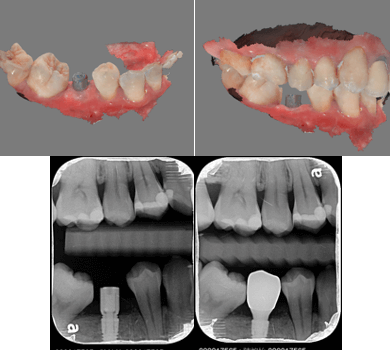

在斷層掃描的 3D 圖疊合牙齒的掃描圖,即可在疊合圖上設計植牙的位置,以此輸出的導引板上設有卡準,植牙器械順著這個卡準,植牙位置超精準,手術速度也會快很多,更能避免傷到重要的神經血管,安全、快速、舒適一次到位。